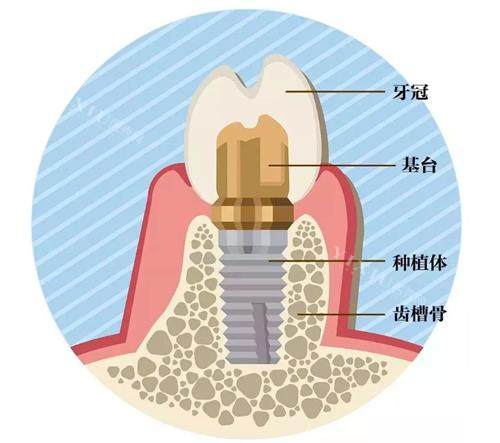

作为院内核心项目,种植牙价格涵盖主流植体品牌,满足不同预算与修复需求,所有价格均包含植体、基台及基础牙冠(全瓷牙冠需额外补差价):